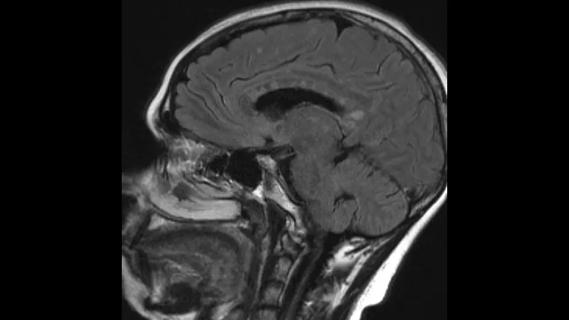

MRI of the brain against black background

Advanced Neuroimaging and Clinical Perseverance Make Sense of a 68-Year-Old’s Progressive Symptoms

A case study in pairing imaging acumen with subspecialty expertise to yield answers and symptom relief